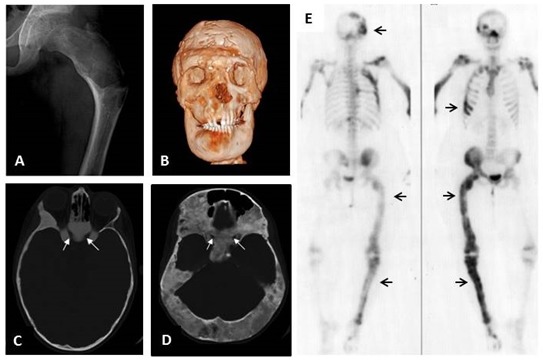

Figura 2. Displasia Fibrosa

A. Fémur proximal con la típica apariencia radiológica de la DF de “vidrio esmerilado”. El fémur presenta la deformidad en coxa vara denominada en inglés “cayado de pastor” la cual constituye la deformidad esquelética más frecuente en pacientes con DF. B. Imagen de TAC tridimensional reconstruida de un paciente de 26 años con afectación cráneo-facial y secreción excesiva de hormona de crecimiento resultando en macrocefalia y deformidad facial severa. C. Imagen de TAC de una niña de 10 años mostrando la típica apariencia de “vidrio esmerilado” en pacientes jóvenes. Es muy frecuente que los canales ópticos estén recubiertos de DF en aquellos pacientes con DF cráneo-facial (flechas blancas). A pesar de ello, la capacidad visual no se suele afectar. D. Imagen de una mujer de 40 años mostrando hallazgos típicos de la DF cráneo-facial en un individuo de mayor edad en la que se visualiza una apariencia más esclerótica con componentes mixtos quístico-sólidos (flechas blancas). En este caso también hay un recubrimiento de DF alrededor de los nervios ópticos sin afectación visual. E. Gammagrafía ósea con Tecnecio-99 postero-anterior (izquierda) y antero-posterior (derecha), mostrando una captación parcheada en las localizaciones afectadas de DF incluyendo el cráneo, las costillas, el fémur y la tibia (flechas), coherente con la naturaleza mosaica de la enfermedad.

Apariencia radiográfica clásica de la displasia fibrosa

Las radiografías en el esqueleto apendicular suelen mostrar lesiones expansivas con una apariencia en “vidrio esmerilado”, adelgazamiento de la corteza, e irregularidades endosteales (Ver Figura 2A). En la región cráneo-facial, la DF suele aparecer en las radiografías convencionales como lesiones expansivas escleróticas, y en la tomografía computerizada suelen mostrar una apariencia de “vidrio esmerilado” (Ver Figura 2C). Con el envejecimiento, las lesiones de DF en el esqueleto apendicular tienden a adoptar en las radiografías una apariencia esclerótica, mientras que en la región cráneo-facial adoptan una apariencia “quística” (Figura 2D).

- La expansión de las lesiones cráneofaciales puede derivar en una deformidad facial progresiva (ver Figura 2B), y en raras ocasiones (normalmente asociada a secreción excesiva de hormona de crecimiento) a la pérdida de visión y/o audición secundarias a la compresión de los nervios ópticos y canales auditivos externos, respectivamente (Cutler et al 2006, Boyce et al 2018).

El exceso de GH no tratado se asocia con la expansión de las lesiones de DF en la región cráneo-facial resultando en macrocefalia y un riesgo aumento en la pérdida de agudeza visual (Boyce et al 2013) (ver Figura 2B).